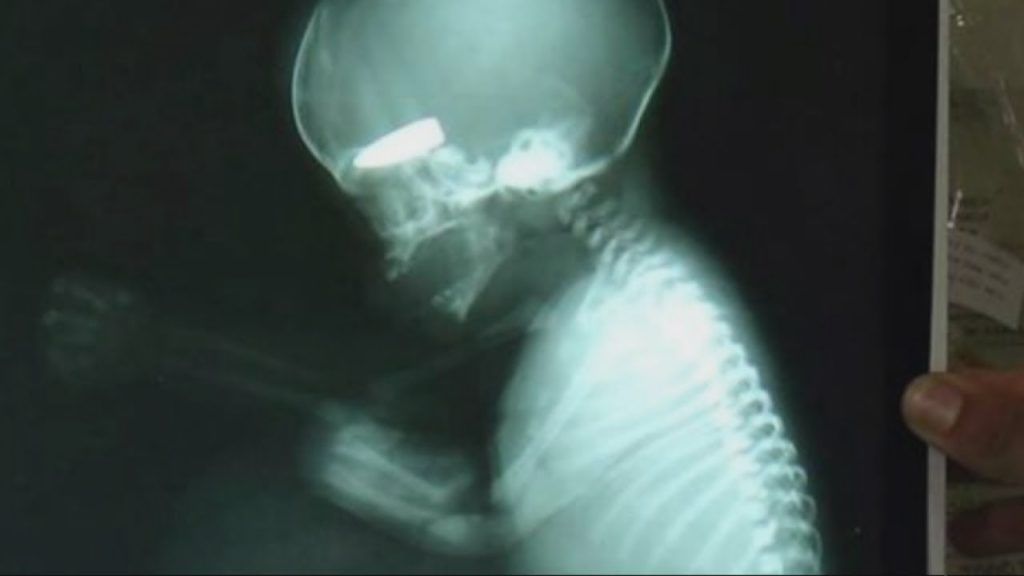

Επίσης αυξάνονται τα στοιχεία σύμφωνα με τα οποία στοχοποιούνται εσκεμμένα έγκυες γυναίκες. Ο Ντέιβιντ Ντοτ, Βρετανός χειρουργός, ήταν μάρτυρας σχετικού περιστατικού στη Συρία, κατά το οποίο χτυπήθηκε σκόπιμα γυναίκα σε προχωρημένη εγκυμοσύνη. Ο Ντοτ έβγαλε μια εφιαλτική ακτινογραφία του εμβρύου, το οποίο πυροβολήθηκε στη μήτρα της μητέρας του από ελεύθερο σκοπευτή.